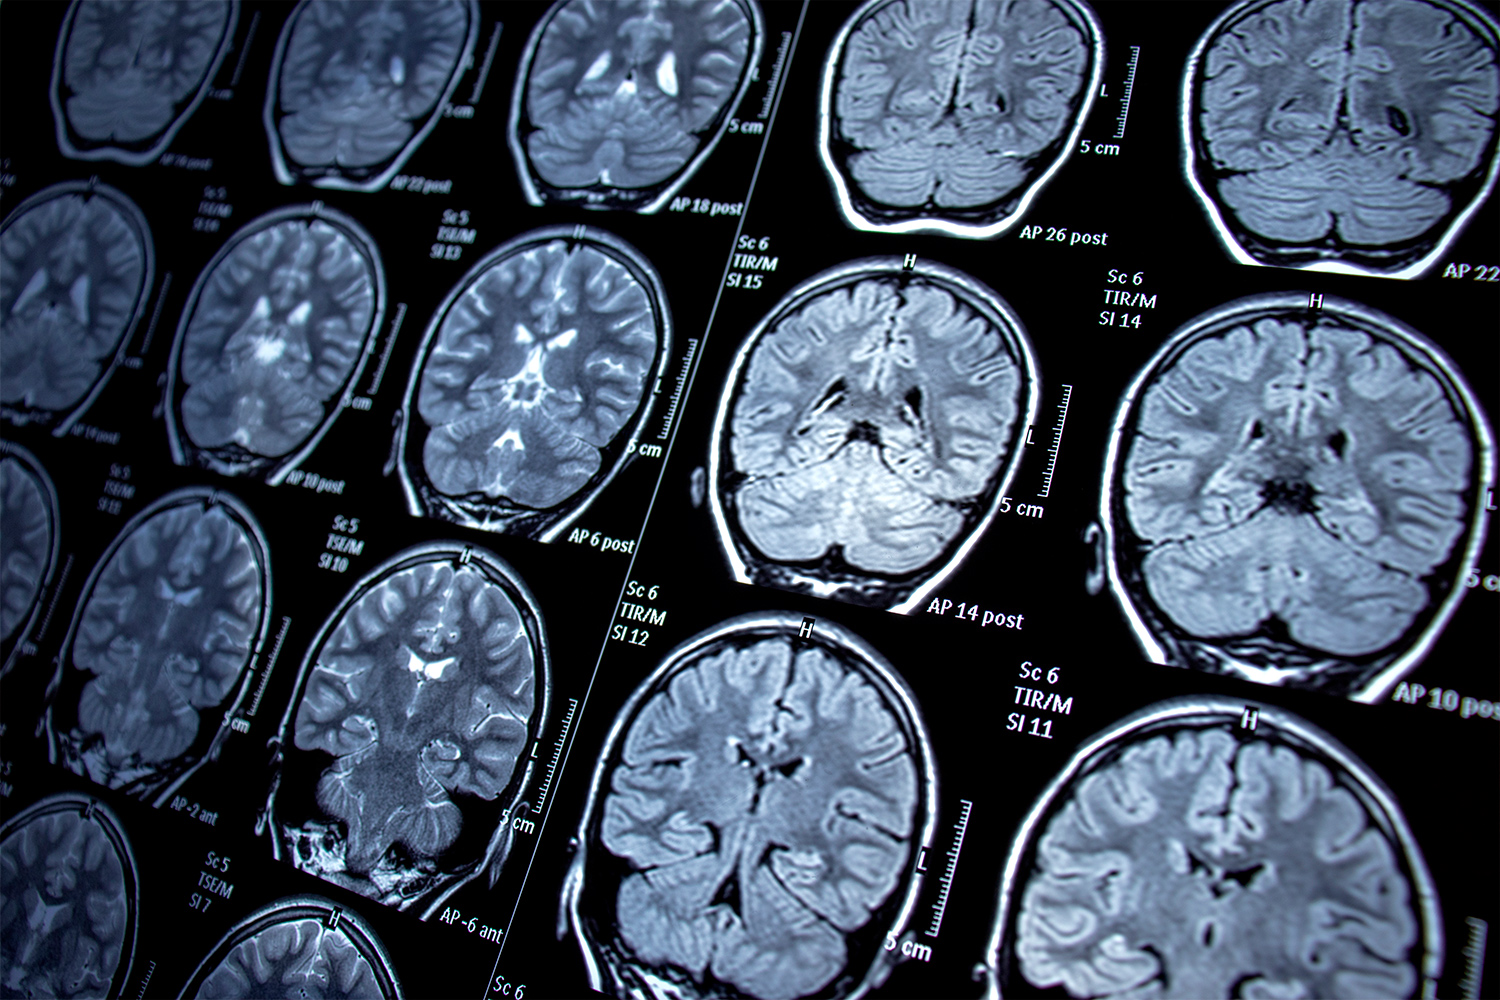

뇌전증은 뇌의 신경세포에서 비정상적인 전기신호가 발생하여 발작 현상이 나타나는 질환입니다. 오늘은 뇌전증의 원인, 증상, 치료 방법 및 일상 생활 관리에 대해 깊이 있게 다룹니다.

뇌전증은 뇌의 신경세포가 비정상적인 전기신호를 발생시키는 상태로, 이로 인해 다양한 발작 현상이 나타납니다. 이는 의식 상실, 행동 변화 등을 포함합니다. 뇌전증은 전 세계적으로 매우 흔한 신경장애 중 하나입니다.